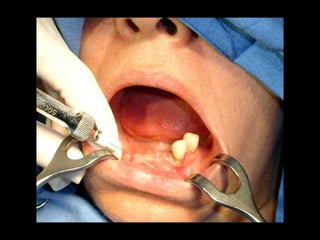

• Paciente de 25 años con

pérdida casi total de